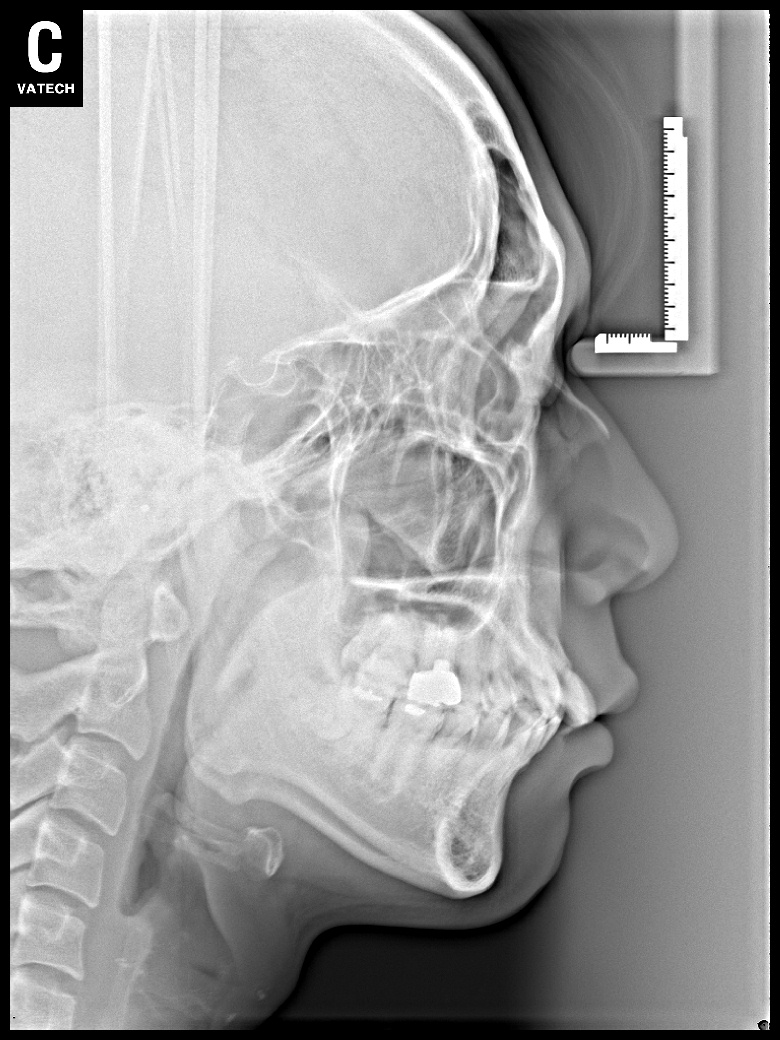

치료 후 사진입니다.